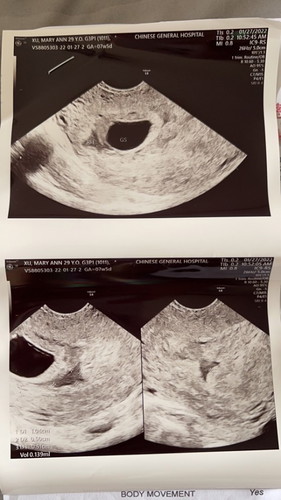

7weeks pregnant but no embryo … Doctors findings consistent with missed miscarriage. So sad😔